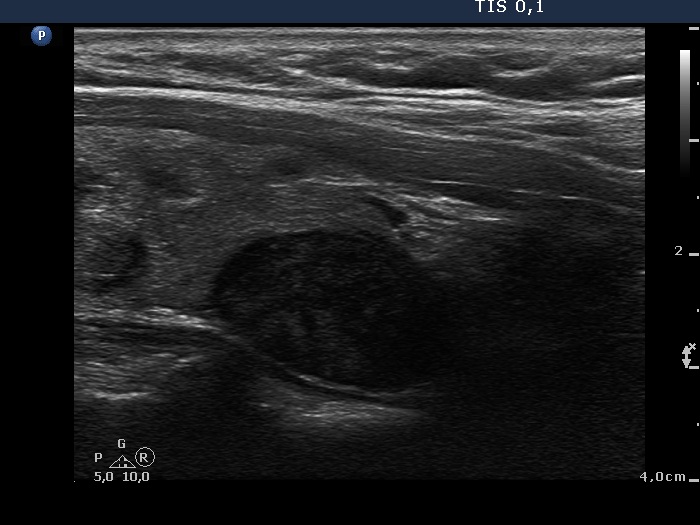

Ultrasonography: The thyroid was echonormal and contained multiple inhomogeneous, hyperechogenic nodules. There was a hypoechogenic lesion in the dorsal part or dorsal to the lower pole of the right lobe.

Scintigraphy disclosed parathyroid lesion corresponding to the mass in the lower-dorsal part of the thyroid.